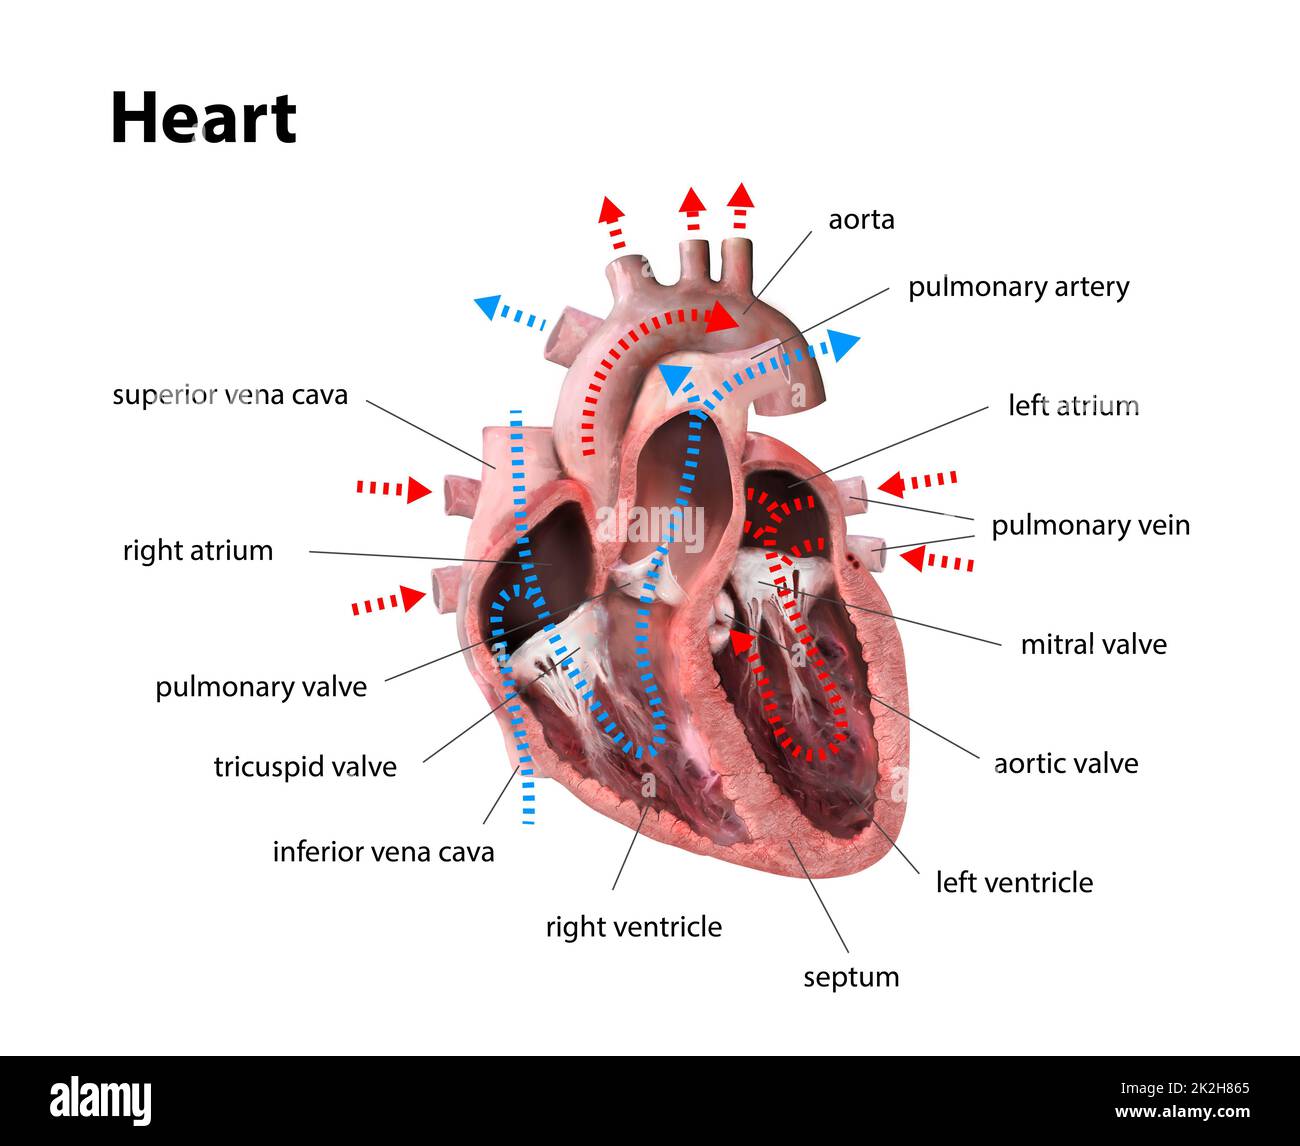

Anatomy of the human heart. Cross sectional diagram of the heart with main parts labeled. Human heart diagram Vector illustration. Educational diagram Stock Vectorhttps://www.alamy.com/image-license-details/?v=1https://www.alamy.com/anatomy-of-the-human-heart-cross-sectional-diagram-of-the-heart-with-main-parts-labeled-human-heart-diagram-vector-illustration-educational-diagram-image551609872.html

Anatomy of the human heart. Cross sectional diagram of the heart with main parts labeled. Human heart diagram Vector illustration. Educational diagram Stock Vectorhttps://www.alamy.com/image-license-details/?v=1https://www.alamy.com/anatomy-of-the-human-heart-cross-sectional-diagram-of-the-heart-with-main-parts-labeled-human-heart-diagram-vector-illustration-educational-diagram-image551609872.htmlRF2R1C00G–Anatomy of the human heart. Cross sectional diagram of the heart with main parts labeled. Human heart diagram Vector illustration. Educational diagram

human heart anatomy. Educational diagram showing blood flow with main parts labeled. illustration 3d render Stock Photohttps://www.alamy.com/image-license-details/?v=1https://www.alamy.com/human-heart-anatomy-educational-diagram-showing-blood-flow-with-main-parts-labeled-illustration-3d-render-image483499245.html

human heart anatomy. Educational diagram showing blood flow with main parts labeled. illustration 3d render Stock Photohttps://www.alamy.com/image-license-details/?v=1https://www.alamy.com/human-heart-anatomy-educational-diagram-showing-blood-flow-with-main-parts-labeled-illustration-3d-render-image483499245.htmlRF2K2H865–human heart anatomy. Educational diagram showing blood flow with main parts labeled. illustration 3d render

human heart anatomy. Educational diagram showing blood flow with main parts labeled. illustration 3d render Stock Photohttps://www.alamy.com/image-license-details/?v=1https://www.alamy.com/human-heart-anatomy-educational-diagram-showing-blood-flow-with-main-parts-labeled-illustration-3d-render-image483495617.html

human heart anatomy. Educational diagram showing blood flow with main parts labeled. illustration 3d render Stock Photohttps://www.alamy.com/image-license-details/?v=1https://www.alamy.com/human-heart-anatomy-educational-diagram-showing-blood-flow-with-main-parts-labeled-illustration-3d-render-image483495617.htmlRF2K2H3GH–human heart anatomy. Educational diagram showing blood flow with main parts labeled. illustration 3d render